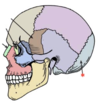

Radius

14

Q

A

Forearm

15

Q

A